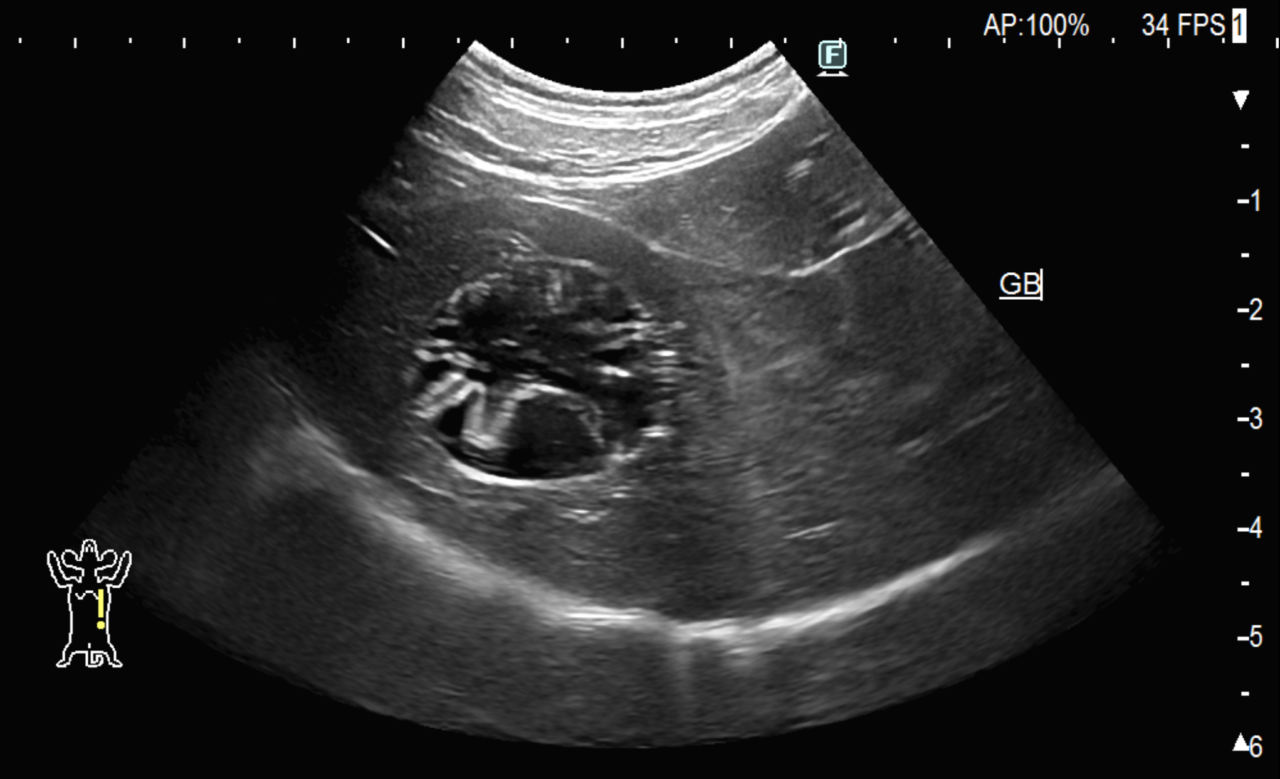

胆嚢粘液嚢腫

高齢犬の定期検診で胆嚢粘液嚢腫が発見されたため、手術が必要か相談したいとのことで紹介来院されました。

血液検査では肝数値の上昇はなく現時点では症状もありませんが、今後さらに高齢になり症状が出てからだとリスクが上がるため手術を行うこととなりました。

待機手術ではなく、胆嚢破裂などの緊急手術では周術期リスクが高くなります。